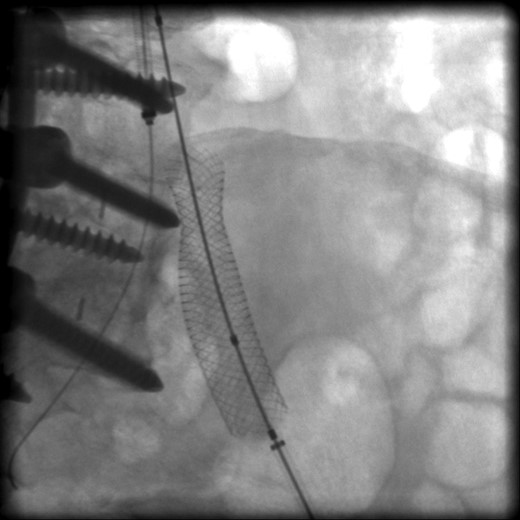

The patient was scheduled for left iliac vein stent placement. During the procedure, impingement was noted upon the posterior aspect of the vein. At this location, there was perforation of a pedicle screw through the anterior cortex of her L5 vertebral body, from prior spinal fusion. This interaction was well visualized during intraluminal inflation of a 12 mm × 40 mm high-pressure balloon (Fig. 2) and was also seen after final stent placement (Fig. 3). Because the screw tip was completely unyielding, a 14 mm × 60 mm Wallstent was used instead of the 16 mm stent we typically use, so as to avoid undue compression of her overlapping right common iliac artery. After the procedure, the patient's symptoms were greatly improved. Follow-up venography performed 4 months postoperatively showed a patent stent with slight eccentric compression at the protruding screw and no evidence of in-stent stenosis.

Intraoperative radiograph showing posterior compression of a wall stent within the left common iliac vein.